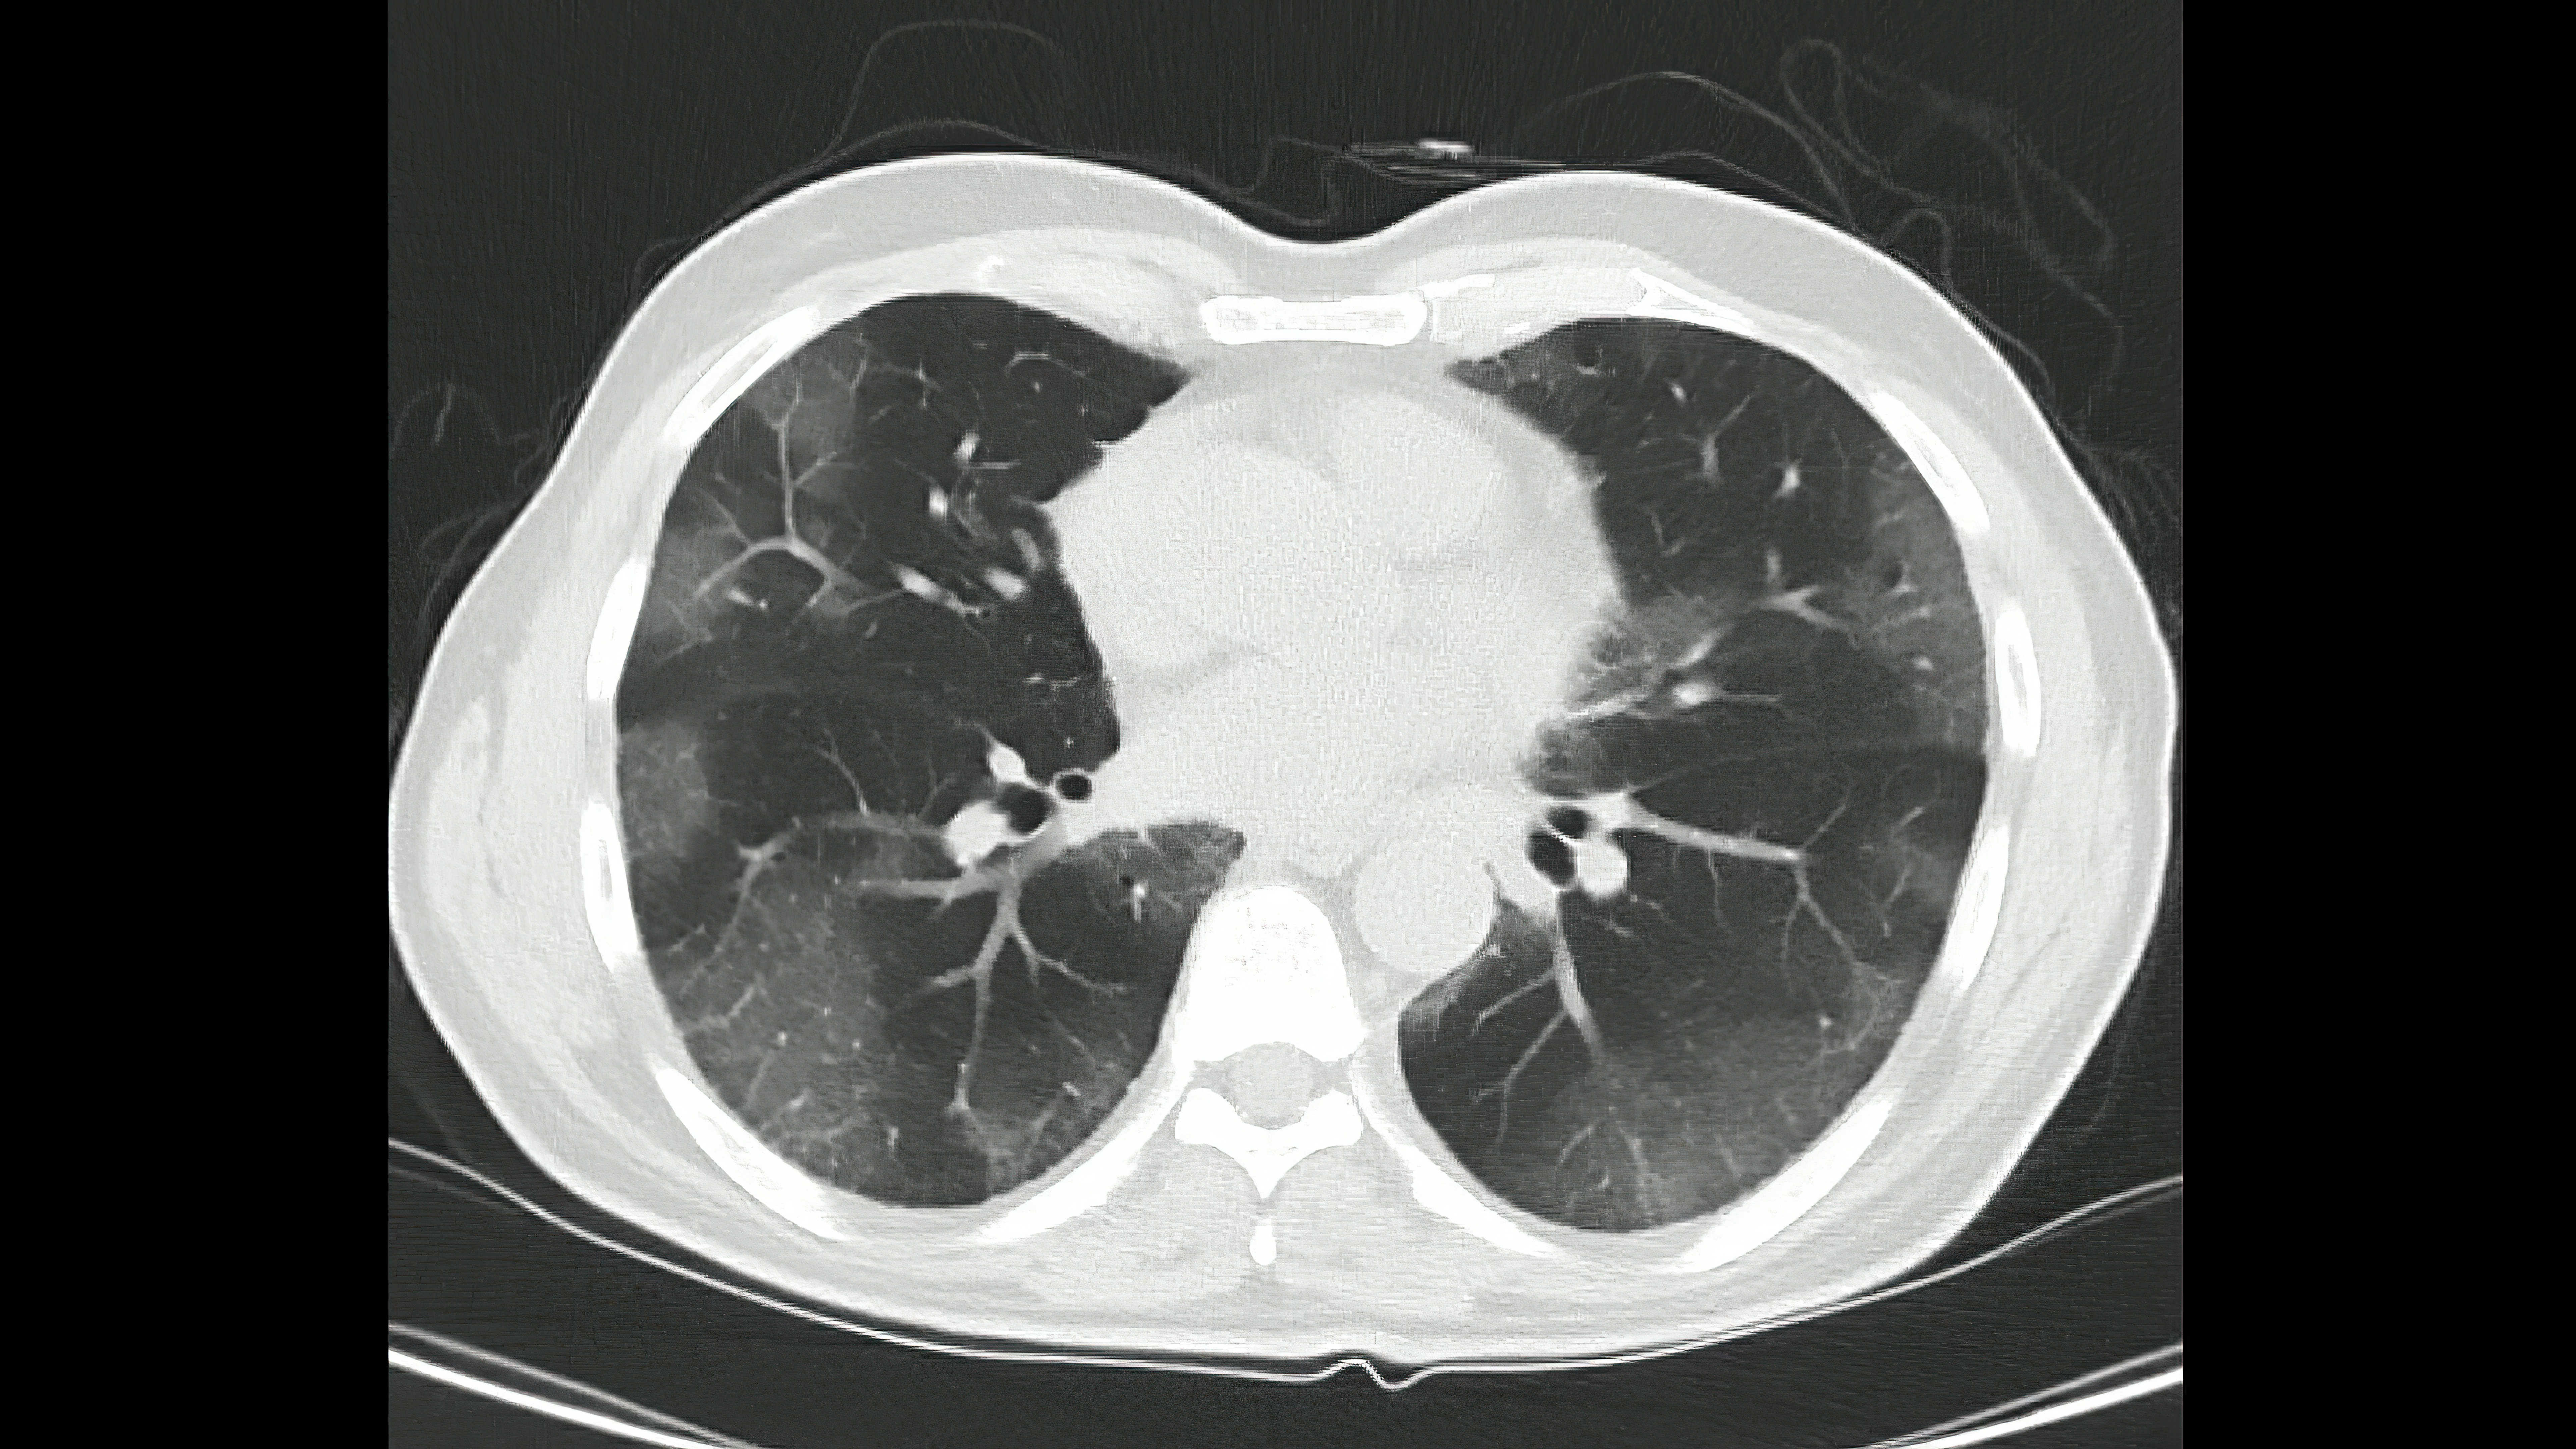

A new study revealed that an emerging artificial intelligence (AI)-enabled software tool led to improved sensitivity, specificity and inter-observer agreement for the diagnosis of indeterminate pulmonary nodules on chest computed tomography (CT) scans.